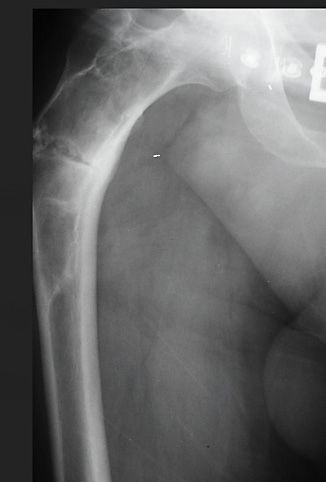

Basit Kemik Kisti

Basit kemik kisti; unikameral kemik kisti veya soliter kemik kisti olarak da bilinir. Kistin etrafı fibrotik doku ile çevrili ve içerisi sıvı doludur. Hastaların %80’i onlu ve yirmili yaşlardadır. Humerus (kol kemiği), femur (uyluk kemiği) üst uçlarında, erişkinde ise kalkaneus ve iliumda (leğen kemiği) görülür.İskelet sistemi büyümesi tamamlandığında genellikle kendiliğinden iyileşir.

Basit kemik kistininvenöz sirkülasyon bozukluğu sonucu geliştiği düşünülmektedir. Venöz kan akımındaki blokaj kemiğin rezorpsiyonuna neden olur. Basit kemik kisti uzun kemiklerin metafizer bölgelerinde gelişir. Yaşamın ilk dekatında daha agresifdir. Genelde asemptomatiktir. Orta derece ağrı, lokal hassasiyet ve şişlik mevcut ise patolojik kırık olduğunu düşündürür. Bulgular olmadan tesadüfen de saptanabilir.

Düz grafi teşhiste çok değerlidir. Düşen yaprak görüntüsü basit kemik kistine özgüdür. Kist kemiğin metafizer bölgesinde meduller boşlukta oluşur ve diafize doğru gelişir. Lezyon balona benzer. Lezyonların %15’i tedavi yapılmadan kendiliğinden iyileşir. Anevrizmal kemik kisti ve fibröz displazi ile karışabilir.

Medikal tedavide lezyon içerisine kortikosteroid enjeksiyonları yapılır. Enjeksiyondan 2 ay sonra radyolojide iyileşme bulgusu yoksa enjeksiyon tekrarlanır. Üç enjeksiyondan sonra iyileşme olmaz ise küretaj ve grefonaj yapılabilir. Ayrıca kemik iliğinden alınan aspirasyon, DBM (demineralized bone matrix), kalsiyum sülfat da enjekte edilebilir. DBM, içerisindeki inorganik mineraller uzaklaştırılmış organik kollajen içerenallogrefttir. Küretaj +kemik grefti ve internal osteosentezkırık riski olan geniş kemik kistleri ve patolojik kırıklar için tercih edilebilecek tedavidir. Böylece kemiğin bütünlüğü sağlanmış olur.